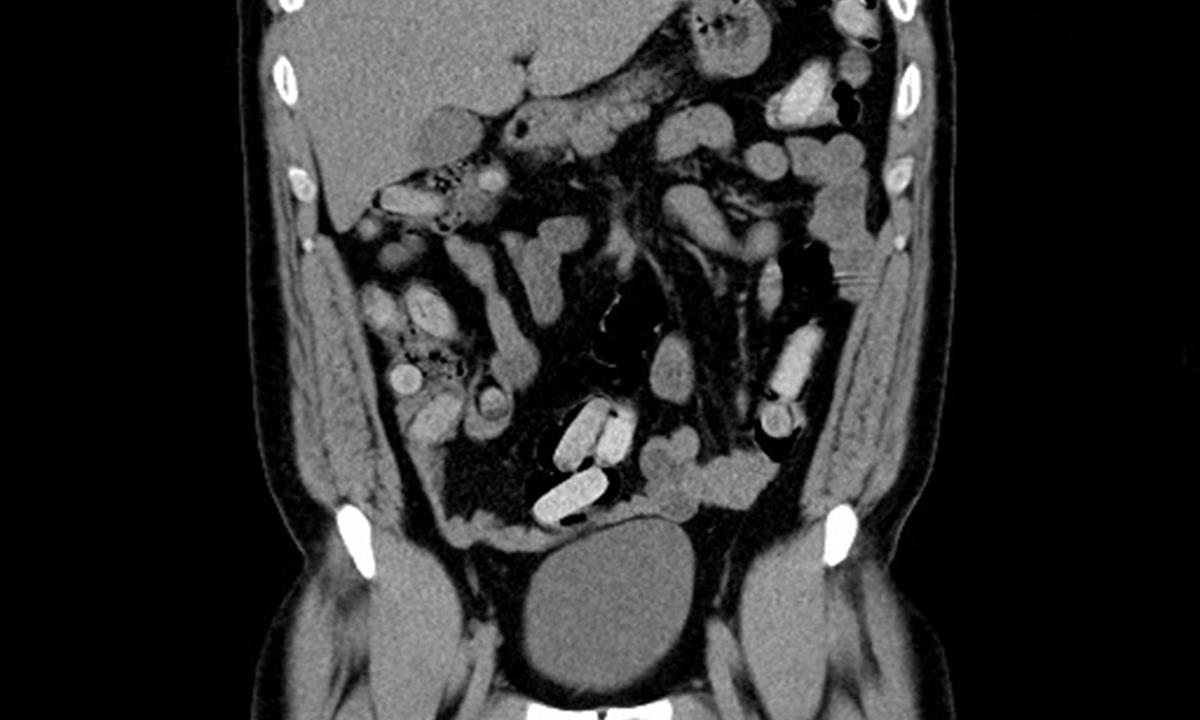

Celníci muže zadrželi a převezli na odborné lékařské vyšetření – počítačovou tomografii (CT). Snímky z CT prokázaly, že se v jeho břišní dutině nacházejí desítky kapslí o velikosti 2x5 cm s neznámým obsahem.

Již během sobotní noci vyšlo na speciální toaletě z těla pašeráka prvních 26 kapslí obsahujících kokain. Další kapsle vycházely postupně v následujících dnech, poslední v úterý večer. Dnešní kontrolní CT vyšetření potvrdilo, že se v jeho tělních dutinách již žádné kapsle nenacházejí.